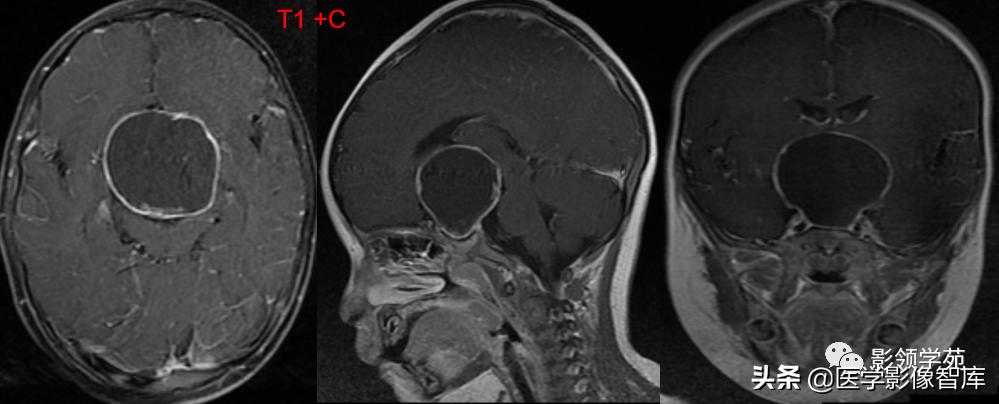

女 61岁 反复头晕3年余

鞍上可见一类圆形均匀稍高密度灶,CT值约47HU,

边界清楚,其内见一小点片状钙化灶;继发鞍上池受压伴变性。

鞍区占位肿块,呈等T1等T2信号,信号均匀,边界清楚。

病灶呈均匀、显著强化(馒头样),以宽基底与前颅窝底相连,

冠状位和矢状位见脑(硬)膜尾征;

肿块突入鞍上池,向上推压视交叉,后缘紧邻垂体柄,与双侧颈内动脉相邻。

(脑膜尾征:增强扫描,肿块邻近的增厚硬脑膜呈窄带状强化,随着远离肿瘤

而逐渐变细。)

颅内动脉走形自然,管壁光滑,未见局灶性异常狭窄或扩大征象。